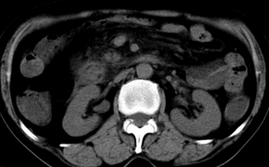

胰头部见结节状高密度影,其前方略可分辨扩强胆部管,平扫到增强始终有,但现在尚难与胃肠造影剂鉴别.

结合病史考虑,1现在引起黄疸体征的原因应该是胆总管胰段结石阻塞,建议局部胃肠造影剂排空后复查.

胆总管末端结石伴肝内胆管扩张合并结石!另:不除外合并胆系感染!

考虑:1、胆道结石伴肝内胆管扩张、积气;胆系感染!2、从平扫、增强片来看,不存在胆管肿瘤征象;3、提介建议:作为影像医师,在做一项检查之前应先熟悉临床医生的目的,象这个病例,检查前就不应喝高密度造影剂,而应充分喝好水就可,要不适得其反,反而较难判断胆总管下段是否有结石。

1)肝内胆管结石,胆总管末端结石伴肝内胆管扩张。2)肝左叶及肝右叶前段增强前后之异常表现,考虑炎性改变,不排除胆管细胞癌。3)脾大。